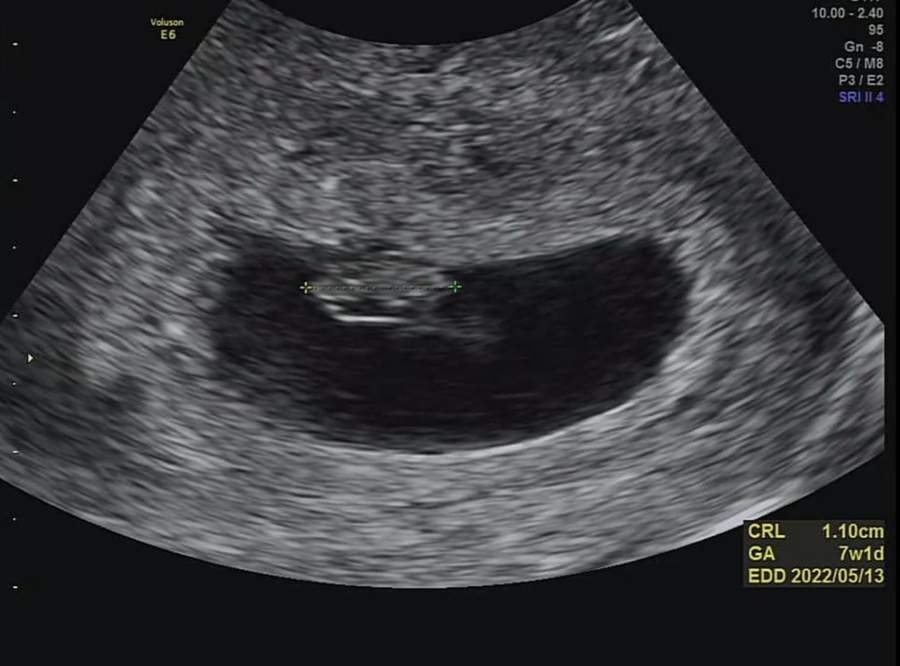

일단 저번보다 아기가 많이 컸다고 비춰주셨어요 아기의 크기는 1.1cm, 7주, 1일 정도로 예상 주수에 맞게 커진다고 합니다.

오른쪽 동그란 거 노른자 같아?동그란 반지 모양 잘 나왔어요 ㅋㅋ

그리고 빛나는 게 아기키라키라 하는 걸 보여줬어요 (웃음)